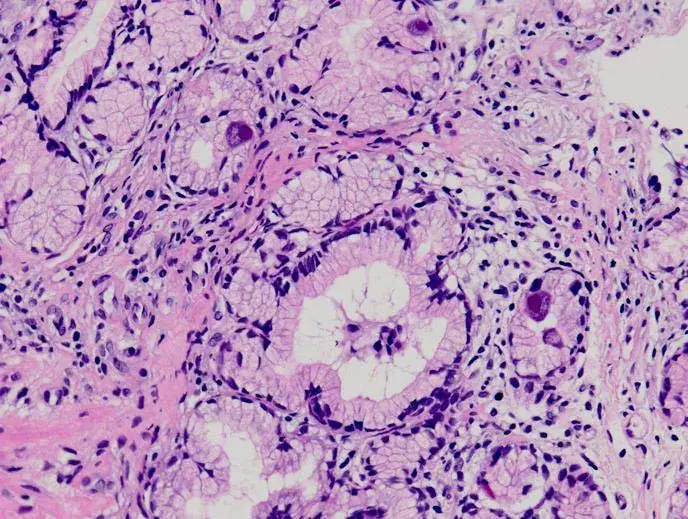

56歲女性,因肺腺癌接受化學治療。上腹悶痛前來就醫。內視鏡檢查發現十二指腸有一直徑約 0.5公分不規則形潰瘍,病理切片檢查如圖所示。最可能的診斷為:

本題考核免疫抑制患者(化療後)消化道潰瘍的病理組織學診斷,核心在於辨識巨細胞病毒(cytomegalovirus, CMV)感染的特徵性「貓頭鷹眼」(owl eye)核內包涵體。

切片為 H&E 染色的十二指腸組織,可見以下重要病理特徵:

- 巨大細胞(cytomegalic cells):組織中可見數個體積明顯放大的細胞,細胞核直徑約為正常細胞的 2–3 倍,呈現典型的 CMV 感染樣態。

- 核內包涵體(intranuclear inclusion bodies):放大的細胞核內含有深嗜鹼性(basophilic)的大型核內包涵體,其外圍有清楚的「透明暈(clear halo)」環繞,整體外觀酷似貓頭鷹眼睛(owl eye appearance),此為 CMV 感染的病理診斷特徵。

- 混合性發炎浸潤:周圍間質可見淋巴球和中性球等炎性細胞浸潤,部分區域出現潰瘍反應性改變。

- 腺體結構:背景可見十二指腸腺體(Brunner's glands)及腸腺結構,整體組織結構仍可辨認。

這些組織學發現(尤其是 owl eye inclusion bodies)具高度特異性,可直接確診 CMV 感染,毋需等待培養或血清學結果。